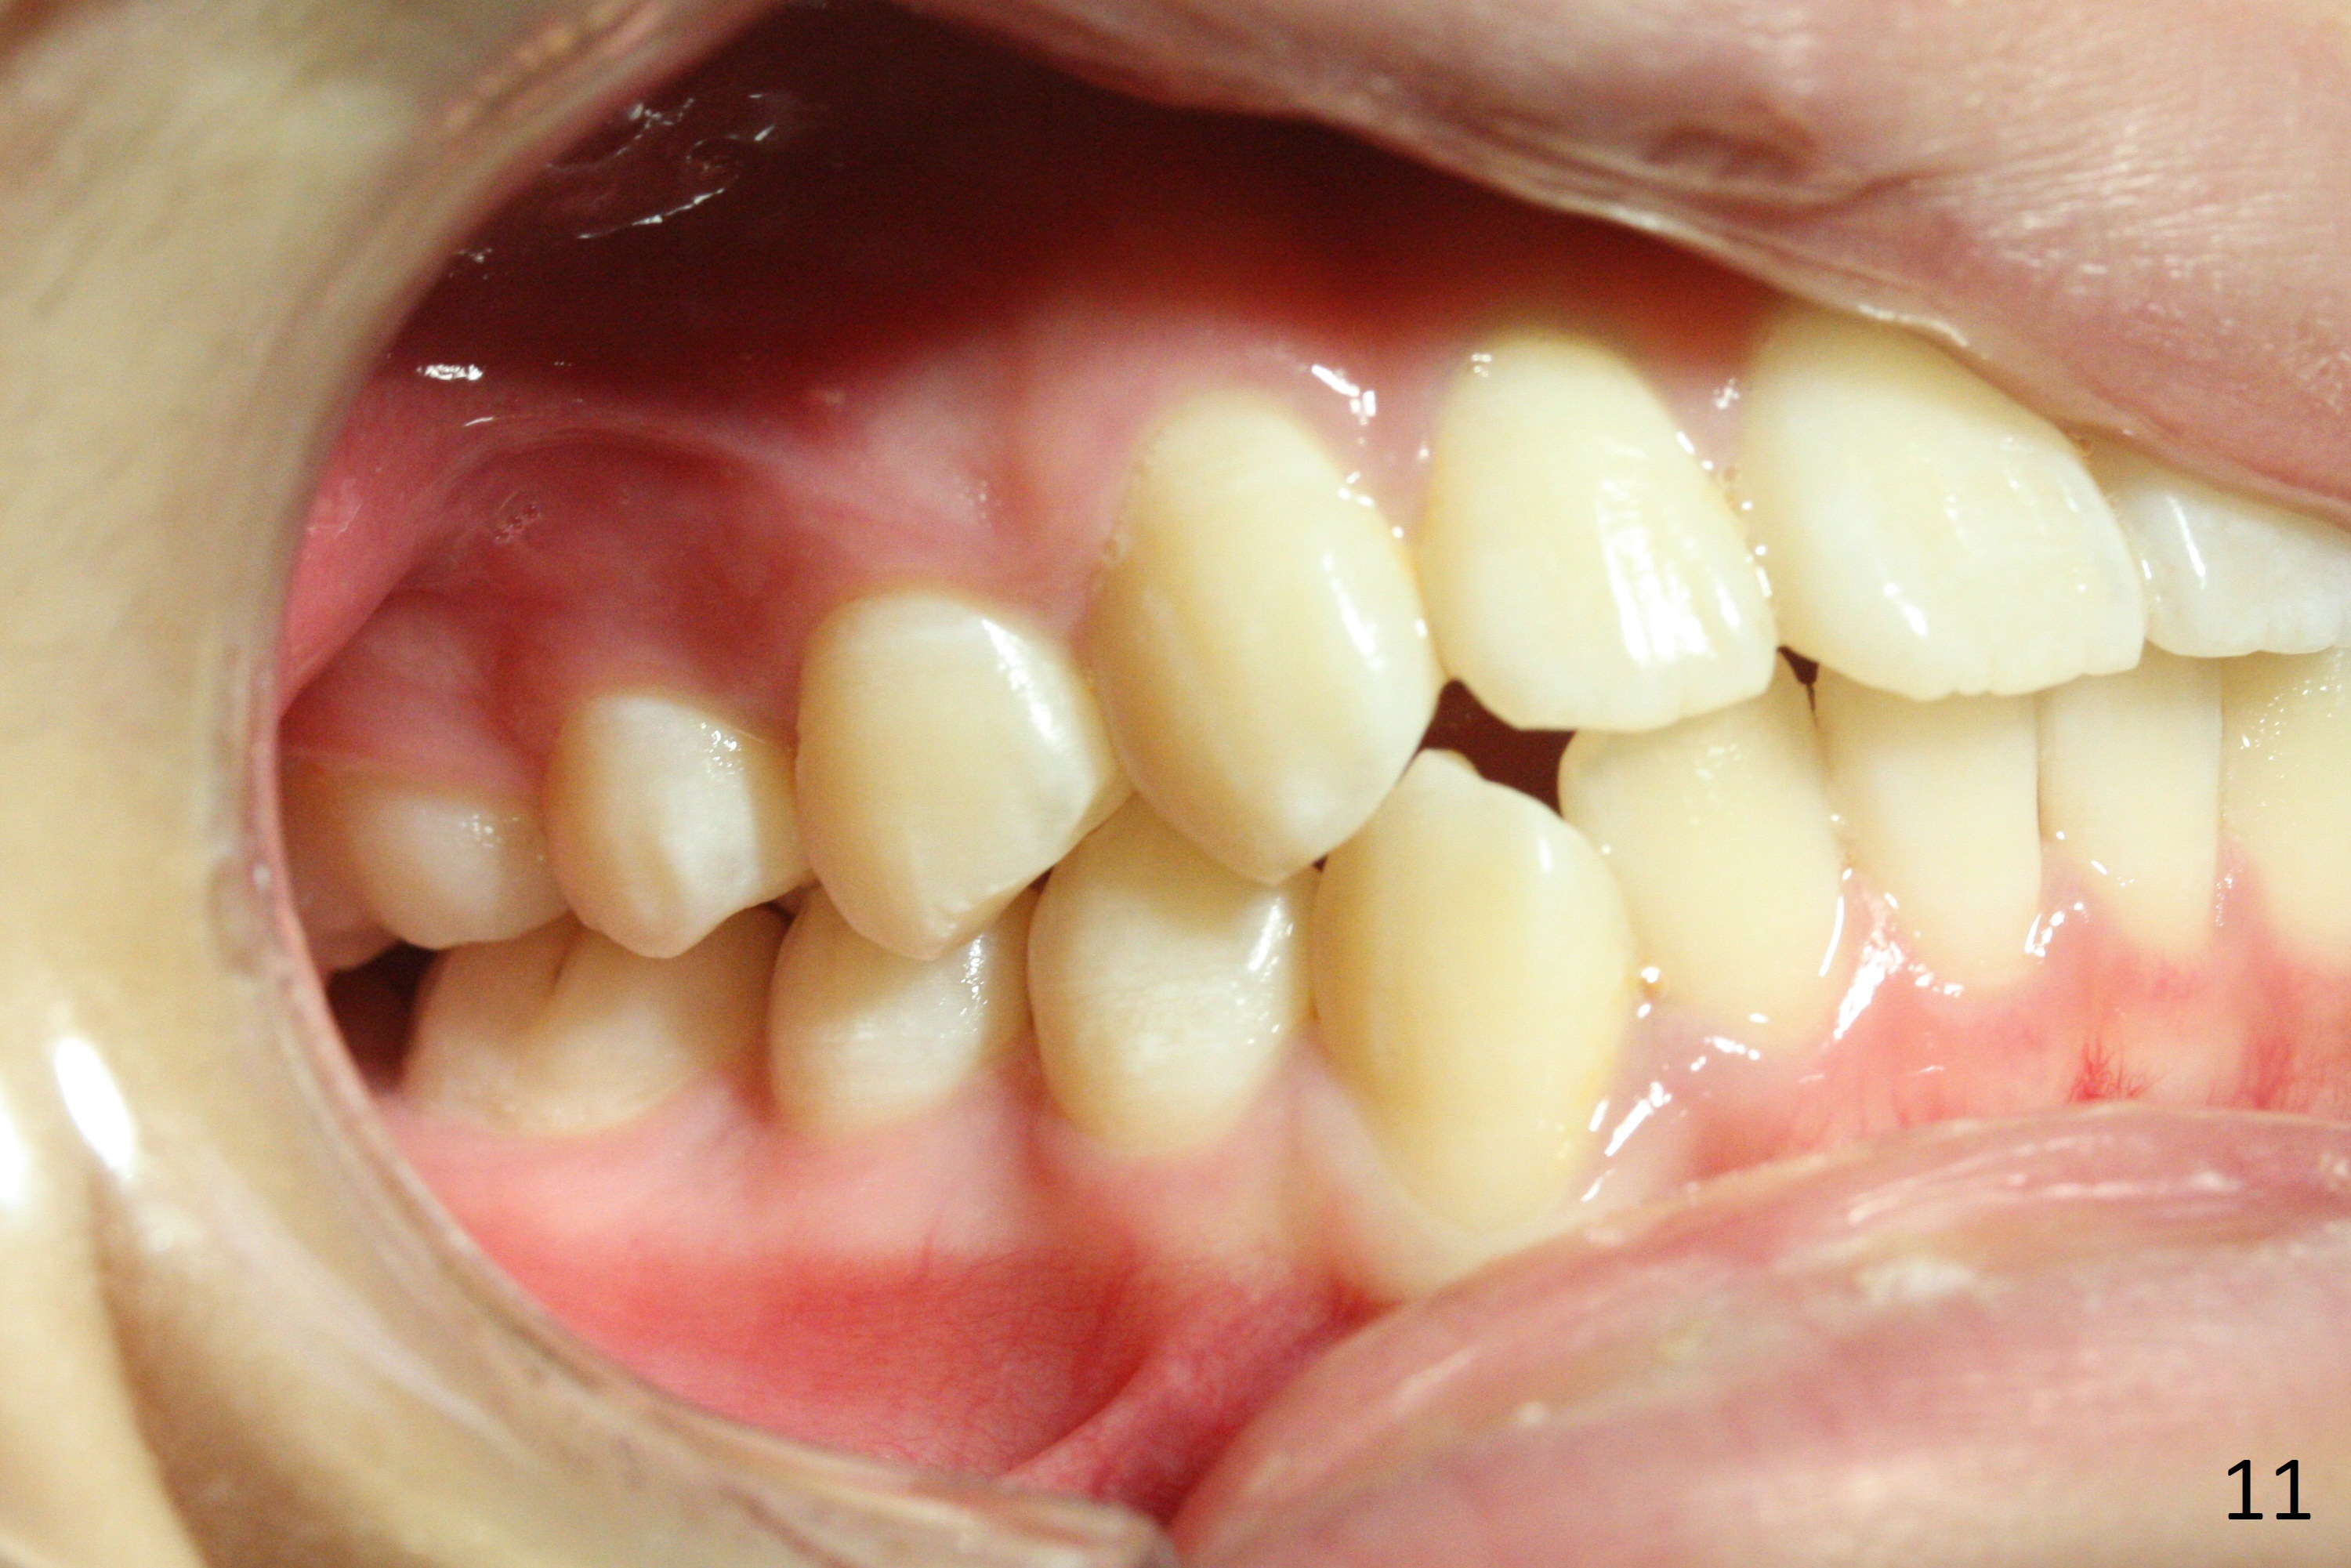

Shallow Overbite

A 12-year-old man has mild lip protrusion (Fig.1,6,7). Orthodontics will be conducted without extraction. Unlike his elder brother, the overbite is shallow. With anterior bracket differential (4-4-5 mm) and mild bimaxillary protrusion, open bite will be created? Or 4-4-4.5mm scheme should be adopted to avoid open bite?